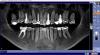

Ksysh Опубликовано 5 сентября, 2011 Поделиться Опубликовано 5 сентября, 2011 Уважаемые стоматологи!Интересно ваше мнение об объеме работ над данной челюстью. Челюсть моя. Работы скорее всего немало. Но хотелось бы исключить лишнюю работу, ибо и так зубов маловато. В особенности интересует нижний левый 5 и 4 зубы. Т.к. именно на них пока сосредоточено внимание врачей моей поликлиники. Подскажите, что с ними сделать. Картинка - скриншот с 3Д снимка...если нужны какие-то виды - заскриншотю. Или выложу весь 3Д снимок - только он много весит. Заранее спасибо. Ссылка на комментарий

Ksysh Опубликовано 5 сентября, 2011 Автор Поделиться Опубликовано 5 сентября, 2011 (изменено) Может быть специалистам будет интересен 3Д-снимок челюсти.Скачать то, что мне записали на диск в клинике можно по это ссылке Скачать файл 3D-snimok_zubi.zip. (весит чуть меньше 300 Мб)Наверняка он более информативен, чем фото, опубликованное ранее. Изменено 5 сентября, 2011 пользователем Ksysh Ссылка на комментарий